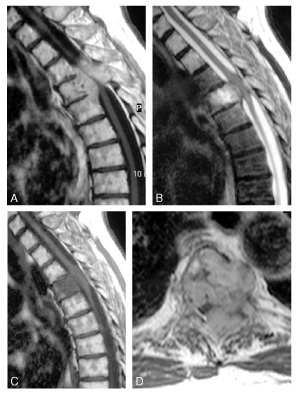

Quel est le diagnostic?

métastase vertébrale avec épidurite, hypo T1 hyper T2 prenant le gadolinium

Diagnostic?

Neurinome en sablier T5 -T6 gauche